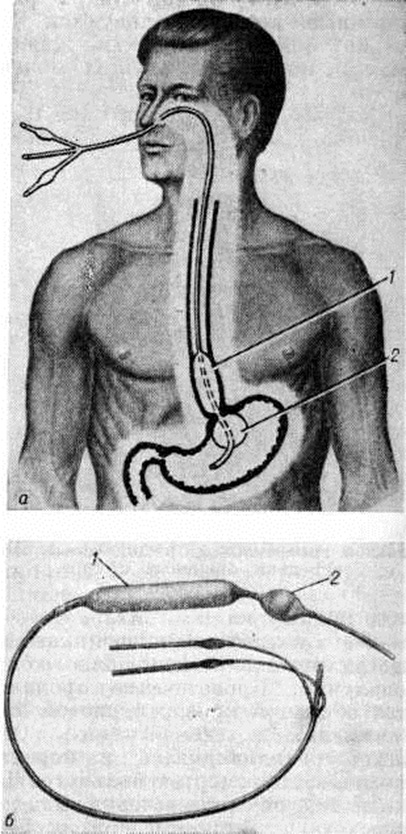

Наиболее действенным. методом консервативного лечения является сдавление вен пищевода зондом Блейкмора (рисунок 7). Последний имеет два пневматических баллона (пищеводный и желудочный) и три просвета. Один просвет предназначен для аспирации желудочного содержимого, а два других — для раздувания желудочного и пищеводного баллонов. Зонд вводят через носовой ход в желудок и через трубку, вмонтированную в стенке зонда, в желудочный баллон нагнетают 50—70 см³ воздуха и подтягивают зонд до ощущения упора в области кардии желудка. Фиксируют зонд к верхней губе лейкопластырем. Затем раздувают пищеводный баллон, вводя в его просвет от 80 до 150 см³ воздуха. Промывают желудок. Если по зонду продолжает поступать свежая кровь, то, очевидно, источником кровотечения являются вены желудка, не подвергшиеся сдавлению. В этом случае следует распустить баллоны и зонд удалить. При остановившемся кровотечении зонд оставляют в пищеводе на несколько часов, периодически распуская манжетки и проверяя, не возобновилось ли кровотечение. Кровотечение из пищевода и кардии иногда удаётся остановить после введения склерозирующих препаратов (например, варикоцида) в просвет варикозно расширенных вен через эзофагогастроскоп.